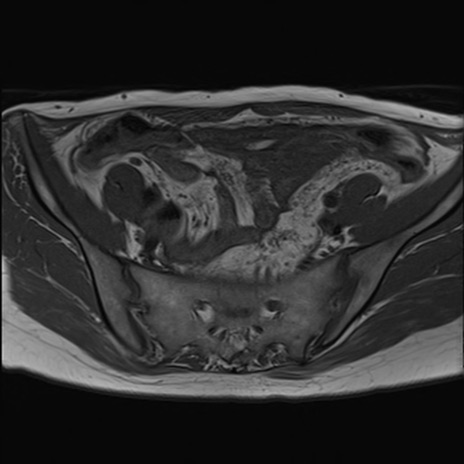

症例39 T1WI(横断像)

MRI(4日後)